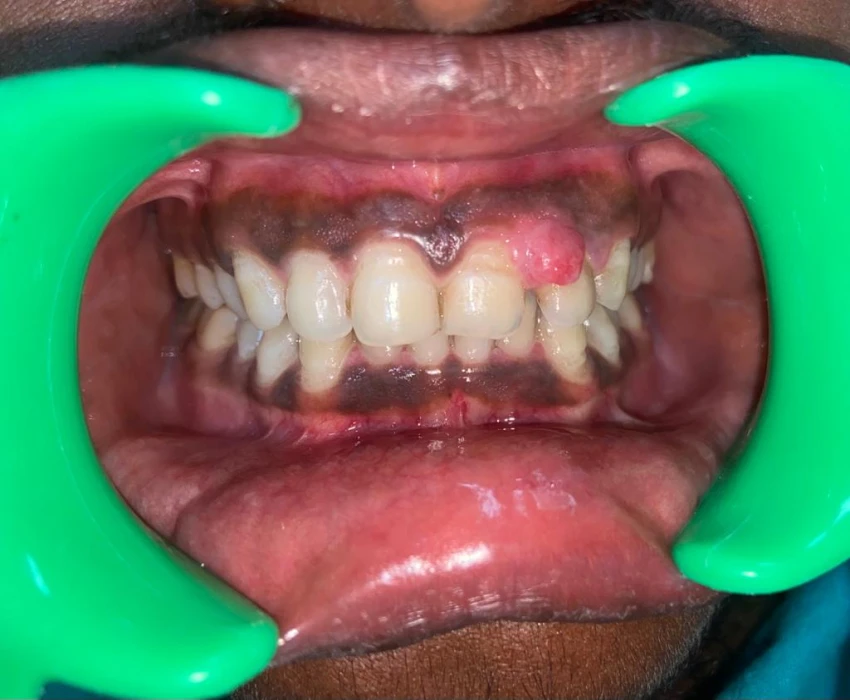

A 19 years old male patient reported to the Department of Oral Medicine and Radiology with a chief complaint of growth in left upper front region of jaw since 2 years. It was diagnosed as Pyogenic Granuloma i.r.t. 22 and differential diagnosis of Peripheral Ossifying Fibroma was given and the final diagnosis came out to be as Peripheral Cemento-ossifying Fibroma as per histopathological analysis.

Peripheral cemento-ossifying fibroma is a reactive gingival overgrowth commonly seen in anterior maxilla. It is a focal, reactive, slow-growing, non-neoplastic tumor-like growth of soft tissue, often arising from the interdental papilla. It may lead to pathologic migration and other periodontal problems.

It can occur at any age but is more common in children and young adults. Female predilection is seen which ranges from 2:1-3:2. Slight predilection for Maxilla is also seen. More than 50% of all cases occur in the incisor-cuspid region. It occurs exclusively on the gingiva and accounts for 3.1% of all oral tumors and for 9.6% of gingival lesions.